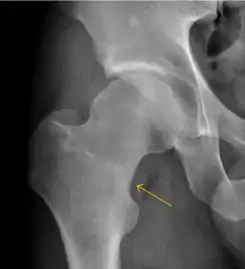

Figure 10:

Stress femoral neck fracture in a young athlete barely visible in X-ray film as a sclerotic line (arrow)[1]

In this case, Tc 99 scintigraphy shows a band of uptake[1]

Furthermore, T1 (left) and DP fat saturated (right) weighted MR images showed the fracture line and a pattern of edema.[1]